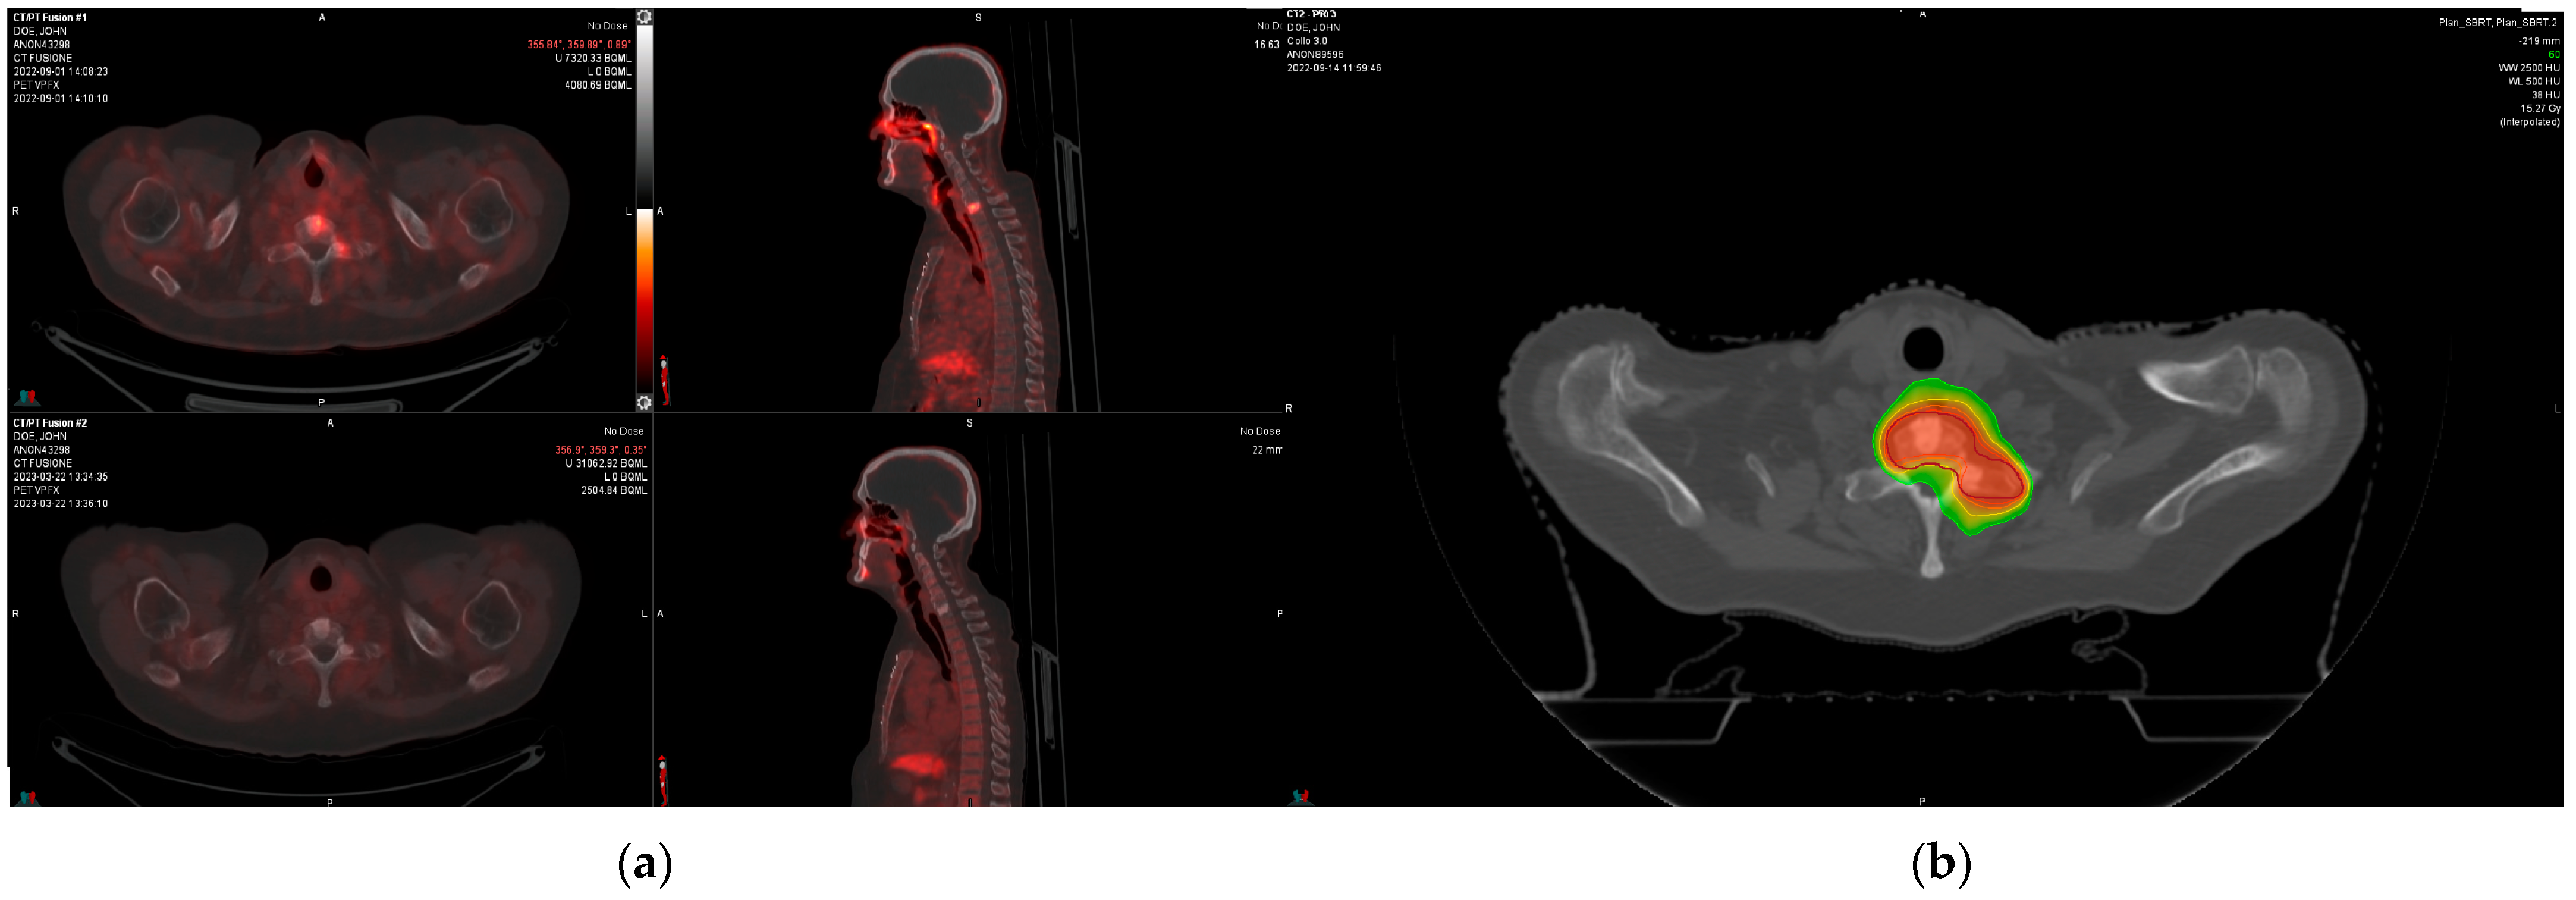

2. Patients and Methods

3. Results